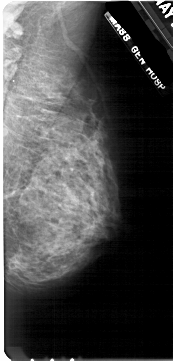

A_1712_1.LEFT_CC

LEFT_CC LINES 4996 PIXELS_PER_LINE 2371 BITS_PER_PIXEL 12 RESOLUTION 43.5 OVERLAY